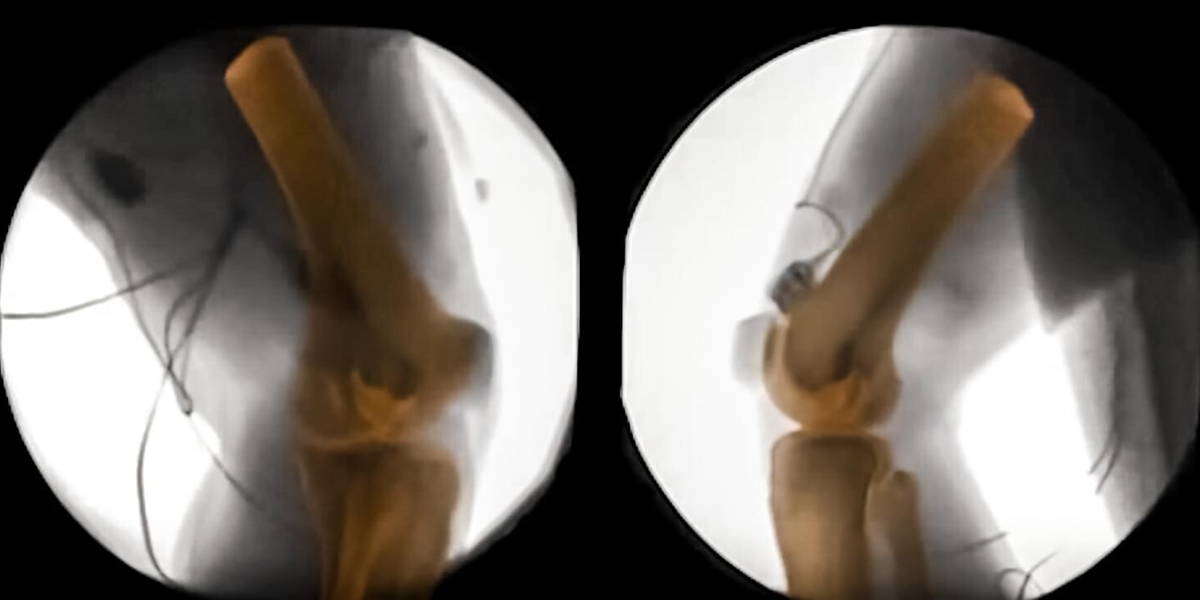

XROMM technology, or X-ray Reconstruction of Moving Morphology, gives researchers a look at bones in motion. This could not only have an impact on human medicine, but also further science’s understanding of animal anatomy. And as if this isn’t enough motivation to advance this technique, the scientists at Brown University also believe that the field of biomechanics could be transformed by it.

X-ray machines have been giving insight into the human body for quite some time now. X-rays can even show movement in unprecedented detail, like blood flowing through a body. One thing such machines can’t provide however, is a 3D-image. Enter CT scans. These scans show detailed, high-quality images of the body in 360 degrees. The scientists at Brown decided to layer these two scans, which led to the XROMM technology and a look at bones in motion.

Understanding how bones move

The new technology helps scientists understand bones more. It, for example, shows how the shape of bones relates to the way the bones move. It also gives scientists a better look at how feet touch the ground, or why prostheses are deemed uncomfortable by amputees. Collaborators at the VA hospital in Providence are already looking at how the residual limb of an amputee moves inside a prosthesis, to try to improve the interface. It could also provide insight as to why women suffer more knee injuries than men. The possibilities seem endless, for humans and animals alike.